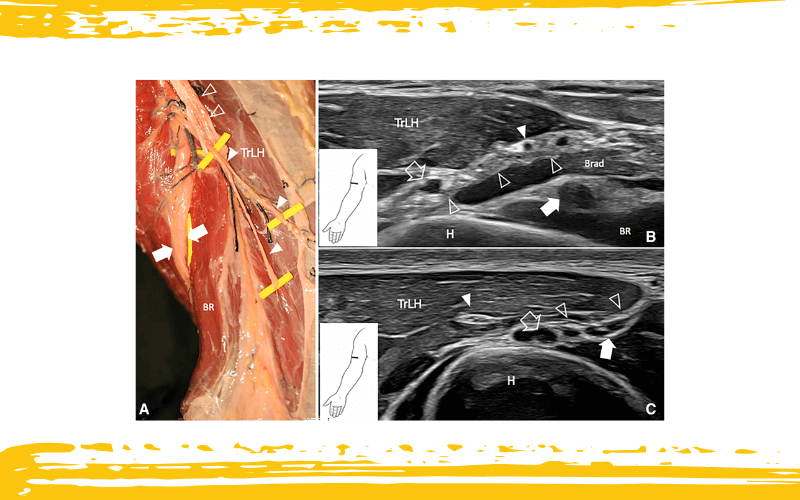

Nervio cutáneo posterior del antebrazo (PCNF).

A. La disección cadavérica del miembro superior muestra el PCNF (puntas de flecha blancas) discurriendo por detrás del septo intermuscular lateral (puntas de flecha delineadas), avanzando hacia la región posterolateral del antebrazo. En contraste, el nervio radial (flechas blancas) perfora el septo intermuscular lateral y se dirige anteriormente y de forma medial.

B. La imagen ecográfica revela el nervio radial (flecha blanca) discurriendo entre los músculos braquial y braquiorradial (BRad) tras perforar el septo intermuscular lateral (puntas de flecha delineadas). Al mismo nivel, el PCNF (punta de flecha) aparece como una estructura fascicular hipoecoica situada por detrás del septo, profunda a la cabeza lateral del tríceps (TrLH), y acompañando a la arteria colateral radial (flecha delineada).

C. Se muestra un trayecto variante del PCNF, en el que el nervio atraviesa la cabeza lateral del tríceps (TrLH) antes de situarse a lo largo del aspecto posterior del septo intermuscular lateral (puntas de flecha delineadas).